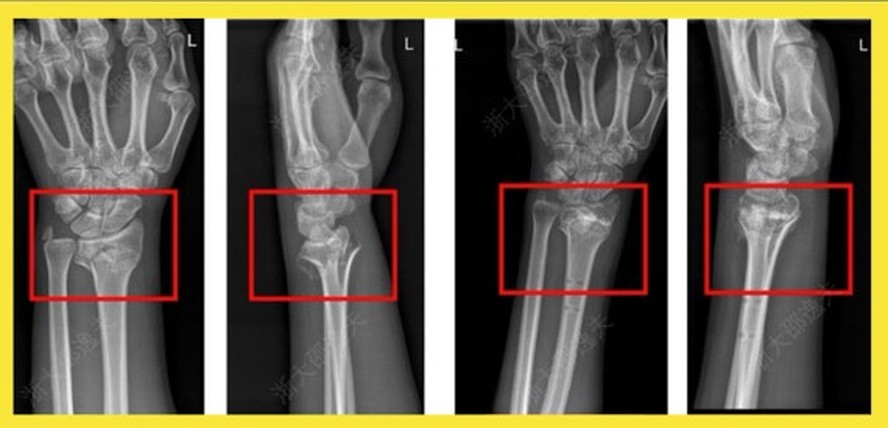

Aplicação com sucesso da Bone-02, a supercola óssea desenvolvida pela China — Foto: Reprodução |

Em caso experimental, um paciente com fratura no punho recebeu uma injeção através de uma incisão de apenas 3 cm e foi curado em apenas três minutos, informou o "Cho Sun Daily". Uma cirurgia para reparar o punho exigiria uma placa metálica e parafusos, cuja remoção exigiria uma segunda cirurgia no ano seguinte. Após um check-up de acompanhamento de três meses, a fratura do paciente havia cicatrizado completamente sem complicações, afirmou a reportagem. Durante os testes, outros 149 pacientes foram tratados com a supercola chinesa, com resultados positivos. O produto já foi patenteado dentro e fora da China.